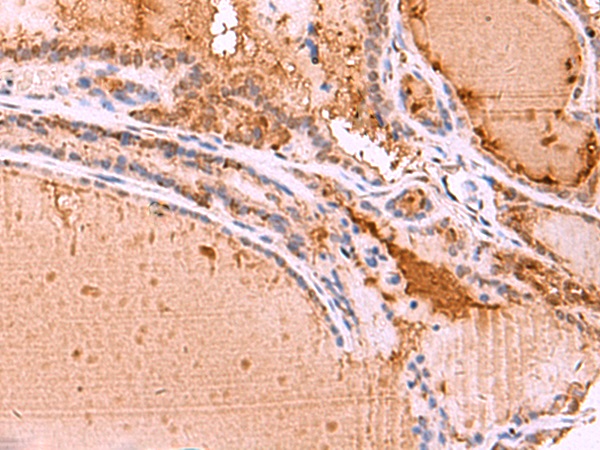

The image is immunohistochemistry of paraffin-embedded Human thyroid cancer tissue using 47642(HTRA4 Antibody) at dilution 1/35.(Original magnification: 200)